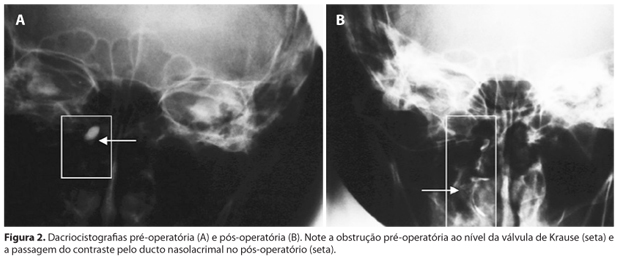

A dacriocistografia realizada após a retirada do tubo de silicone demonstrou passagem do contraste com discreto estreitamento na porção inicial do ducto nasolacrimal nos 13 pacientes com irrigação positiva (Figura 2).

Foi solicitado controle radiográfico (dacriocistografia) após a retirada do tubo de silicone.